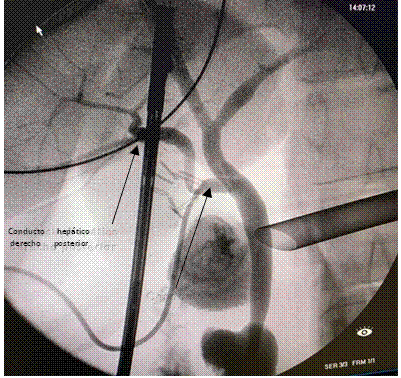

Se presenta la colangiografía intraoperatoria obtenida durante la colecistectomía laparoscópica de una paciente de 58 años con el diagnóstico de colecistitis aguda.

Se evidencia una variante de la vía biliar tipo de F de la clasificación de Blumgart, es decir el drenaje del conducto hepático derecho posterior a la altura o dentro del conducto cístico. Poco frecuente 0,58% (2), es tal vez la de mayor riesgo de lesión durante la colecistectomía laparoscópica.